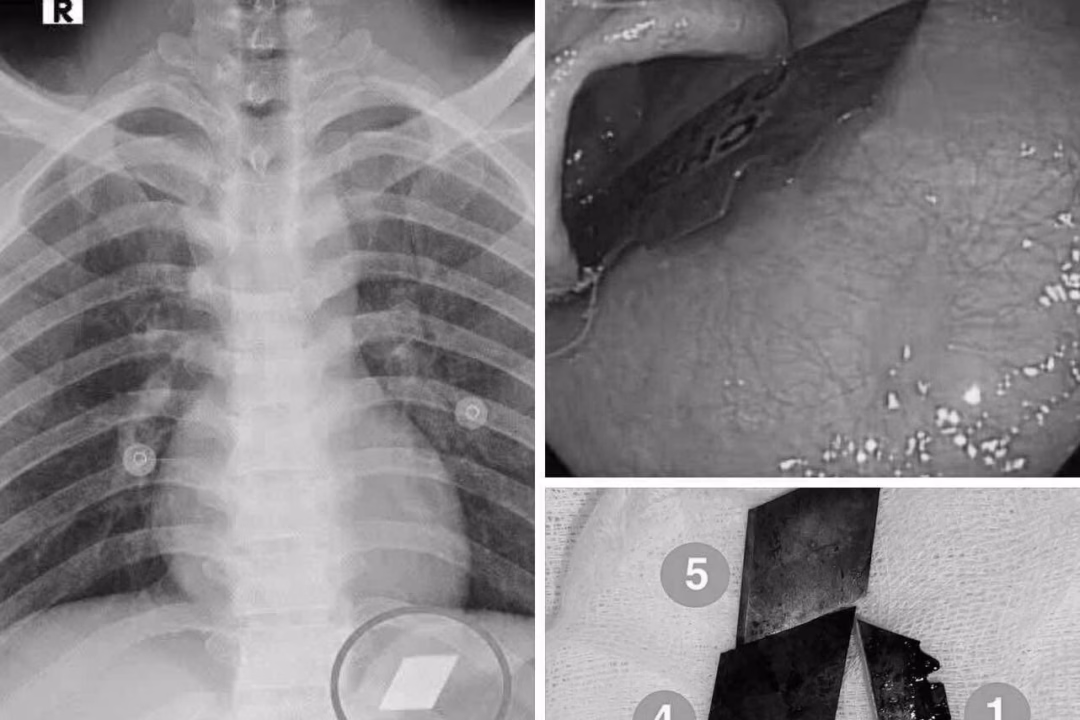

Ngày 10/7, Khoa Hồi sức cấp cứu – Bệnh viện Đa khoa Bình Dương đã tiếp nhận một trường hợp cấp cứu hiếm gặp. Bệnh nhân P.V.L, 26 tuổi, được nhập viện trong tình trạng nuốt nhiều dị vật kim loại sắc nhọn, bao gồm dao rọc giấy và dao lam.

Qua thăm khám và chụp X-quang, các bác sĩ đã phát hiện ra các dị vật cản quang tại vị trí dạ dày. Bệnh nhân ngay lập tức được chỉ định nội soi cấp cứu để gắp bỏ dị vật. Quá trình nội soi được thực hiện dưới sự phối hợp chặt chẽ giữa ê-kíp nội soi và gây mê, các bác sĩ đã thành công gắp 4 lưỡi dao rọc giấy ra khỏi dạ dày và một phần lưỡi dao lam mắc tại vùng hạ họng – miệng thực quản.

Sau thủ thuật, bệnh nhân được theo dõi sát và đã ổn định sức khỏe, xuất viện trong tình trạng an toàn. Theo bác sĩ Phan Lê Quốc Du, Khoa Thăm dò chức năng, Bệnh viện Đa khoa Bình Dương, các dị vật sắc nhọn trong đường tiêu hóa đòi hỏi phải can thiệp nội soi kịp thời. Nếu không lấy ra kịp thời, dị vật có thể gây thủng thực quản, thủng ruột, dẫn đến biến chứng nặng nề, thậm chí tử vong.